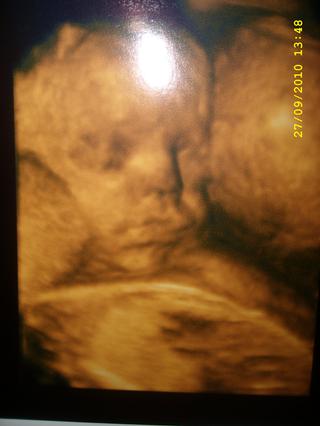

Holky díky 😉 Holčička se ukazovat taky nechtěla, ale nakonec se trochu povedlo 😵